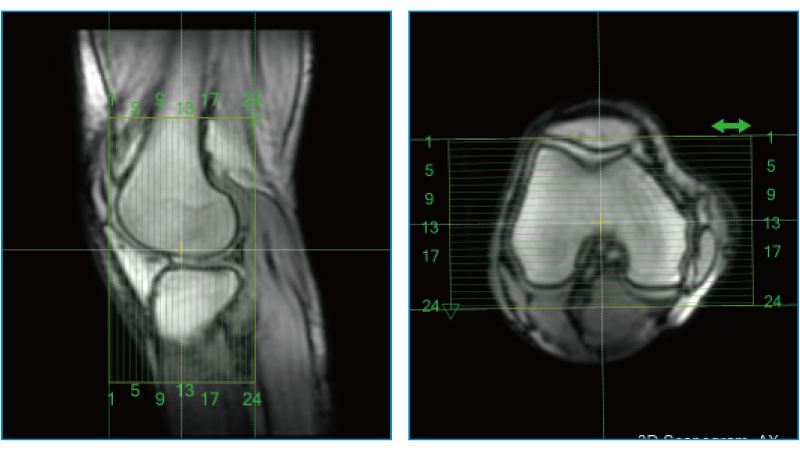

AutoPose Knee

スライスライン設定サポート機能"AutoPose"は、Scanogram撮像終了と同時にスライスラインを設定します。